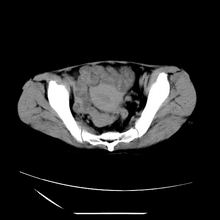

女性,41岁,发现左腹部包块3年,现行ct检查,检查前做过静脉肾盂造影。

左侧低密度区是脂肪密度,中间可见条索状软组织样密度影,现主要想知道左肾前下缘圆形软组织样密度影,内见低密度水样密度影,这是什么?

脾脏增大,左肾后方脂肪增多,脊柱前方脂肪增多,左肾窦脂肪增多,左肾变形,双肾积水以左侧为著,左肾内侧及上方见环形软组织肿物影,内部低密度区,考虑1盆腹腔/腹膜后及左肾窦脂肪增多症2左肾内侧病灶可能为左肾上腺病灶,可能为脂肪增多的原凶